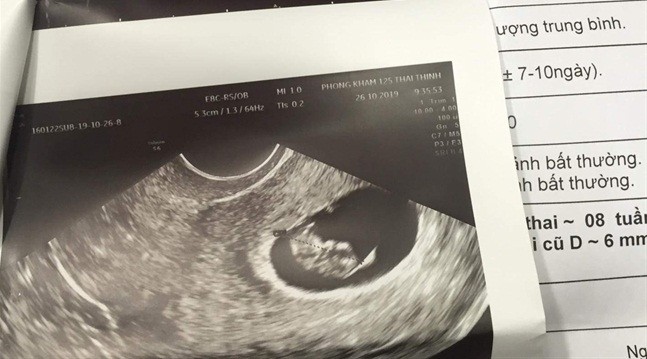

Kết quả siêu âm cho thấy chị A. mang thai 8 tuần

Khi về nhà, chị A bị mệt mỏi, khó thở, buồn nôn và các biểu hiện mỗi ngày một nặng hơn. Do sức khỏe không cải thiện, ngày 24/10, chị A đi khám tại một BV tư ở Hà Nội. Kết quả là chị A. đã có thai được 8 tuần. Như vậy, vào thời điểm hút mỡ bụng, chị A. đã mang thai hơn 4 tuần.

Ngày 28/10, cả hai Thẩm mỹ viện và chị A. đã đến một bệnh viện tư ở TP.HCM để kiểm tra. Bác sĩ cho biết, chị A có thai 8 tuần.